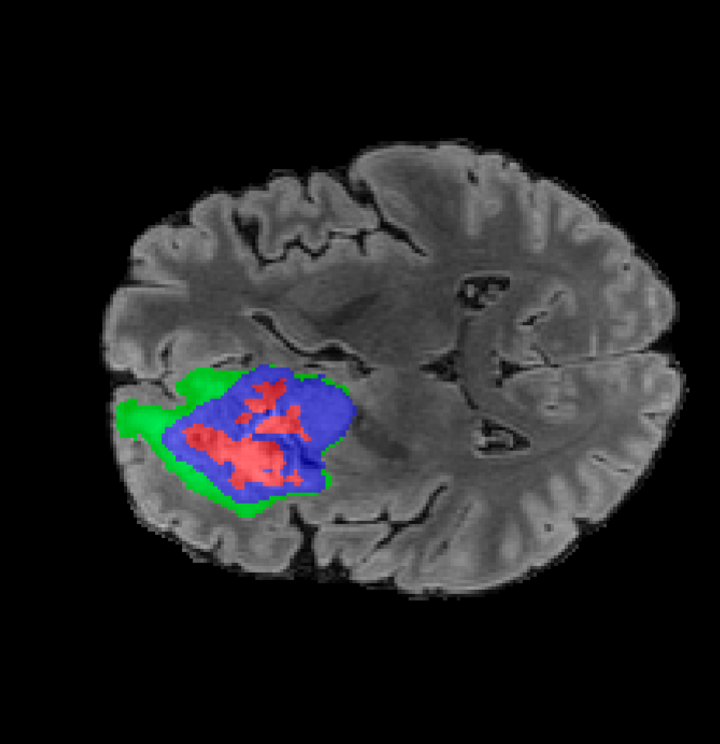

BRATS. The largest public dataset of brain tumours consisting of 5,880 MRI scans from 1,470 brain diffuse glioma patients, and corresponding annotations of tumours[4, 45, 5]. All scans were skull-stripped and resampled to 1 mm isotropic resolution. All images have a resolution of 240 240 155, and we use the flair T2 sequence. Tumours are annotated for 3 classes: Whole Tumour (WT), Tumour Core (TC), and Enhanced Tumour Core (ET).

Tumour Information Preservation. For the brain tumor segmentation, we use a Swin UNETR model[28, 70], trained with random rotation, and intensity as data augmentation. On the test set with human ground-truth annotations (), the brain volumes generated from single slice input preserve the volume of the different tumour components (paired t-test, for all 3 classes). In Figure 4, we highlight the tumor profiles of the generated MRIs compared to the ground truth tumour profile. The real MRI Dice score in the test set is 85.15 while the generated MRIs from a single slice have a dice score of 83.09. This shows how the generated MRIs indeed preserve the tumor information and can act as an affordable and informative pseudo-MRI, before conducting an actual costly MRI examination in hospitals. More detailed results are provided in supplementary material.